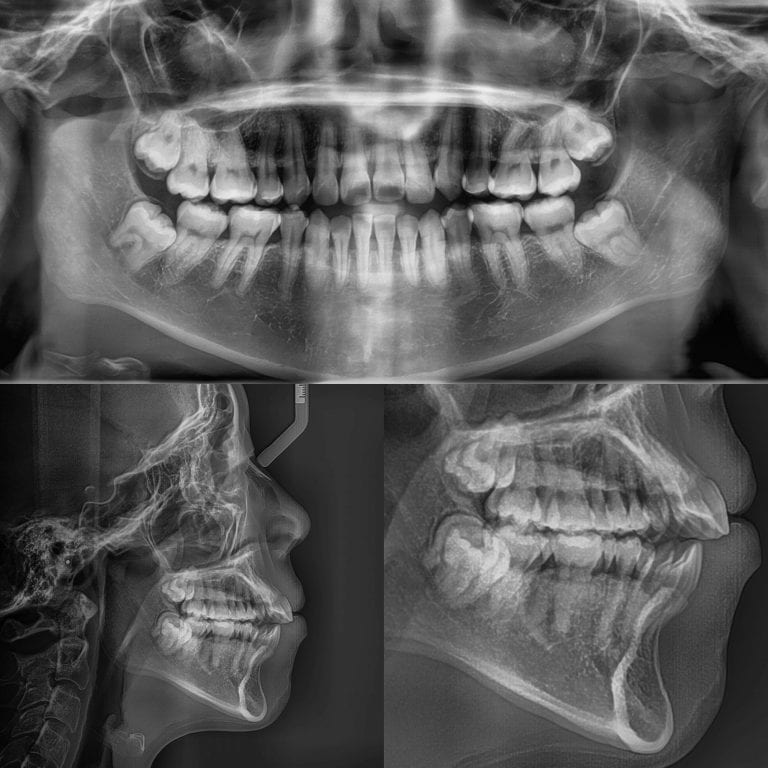

- A front-runner technology in 3D imaging is i-CAT, an advancement in dental X-rays. i-CAT produces 3D CT scans to provide images of the entire mouth structure, hard and soft tissues, and the surrounding facial structures. Dental practitioners rely heavily on clear and accurate images to diagnose dental problems and provide precise treatment, and i-CAT 3D imaging offers superior imaging capabilities. It produces less harmful doses of radiation than traditional X-rays while producing multi-angled data images, allowing dental practitioners clear and comprehensive views of patients’ mouths.

Benefits of i-CAT 3D Imaging

Complete and Accurate View

i-CAT technology gives dental practitioners a precise and vivid view of patients’ teeth, bone structure, soft tissues, and airways. This results in more straightforward diagnosis and treatment planning, more accurate implant placement, and shorter treatment times. This is particularly important when dealing with complex cases like common problems of airway extraction.